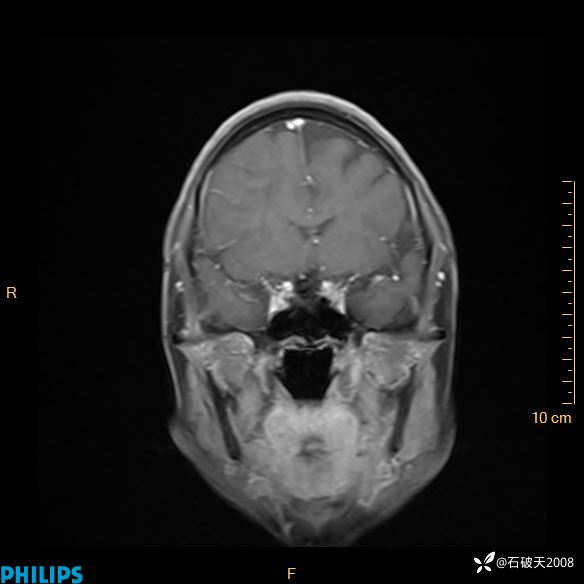

2024.2.21MR

增强冠状位